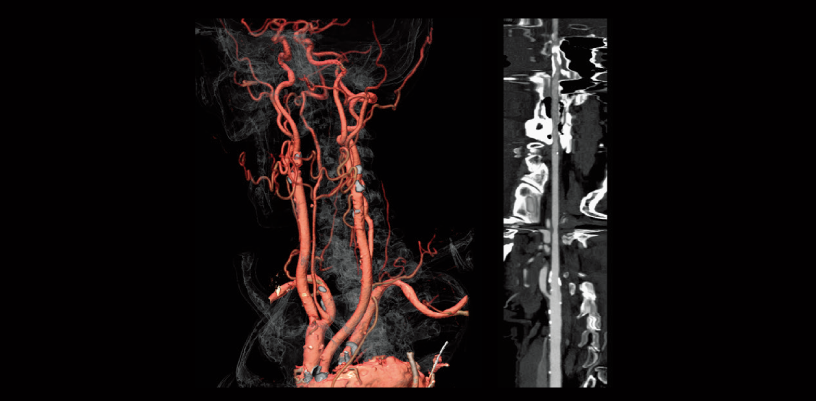

Common carotid artery stenosis